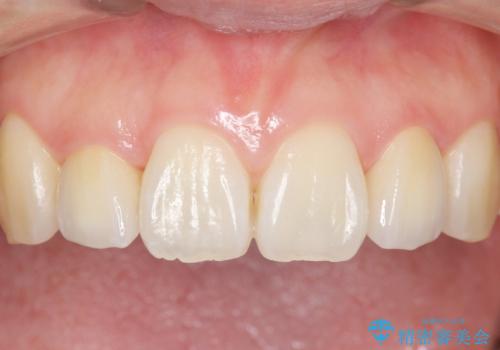

自然な仕上がりにご満足頂けました。

「自分でもどこを治したのかわからないくらい自然!」と喜んで下さいました。

クラウンの種類:オールセラミッククラウン スペシャル